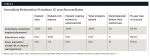

A preexisting defect is present in which both vertical and horizontal bone volume are deficient, and an implant cannot be placed into the residual ridge in the proper position to support an esthetic emergence profile.24 This procedure requires a separate bone replacement/graft procedure prior to implant placement.28-30 In addition, the author advocates an incision technique, a nonabsorbable titanium-reinforced membrane, and, when possible, an amniotic/chorionic membrane.31 This is to support rapid soft-tissue healing and maturation by providing different types of collagen and cell adhesion bioactive factors and aiding in proper alveolar reconstruction of the grafted ridge (Table 1; Figure 8 and Figure 9).

This article will discuss the success rates of more than 5000 implants placed into extraction, edentulous, and sinus-grafted sites, based on earlier reports presented by the author.3,11 These cases follow the management protocols outlined for the 4 types of residual alveolar defects remaining on the facial of an implant placed in the proper spatial arrangement in the tooth positions to be replaced with dental implants, in the esthetic zone and both the maxillary and mandibular arches. For a 15-year period, observation has been documented, in regard to implant fixture stability and long-term integration, and the success rates observed can be seen in Table 2 through Table 4.